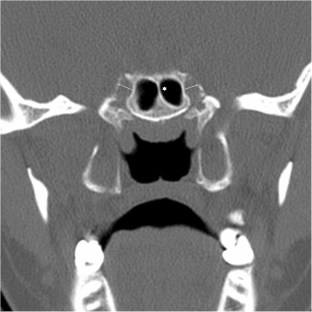

Fig. 3